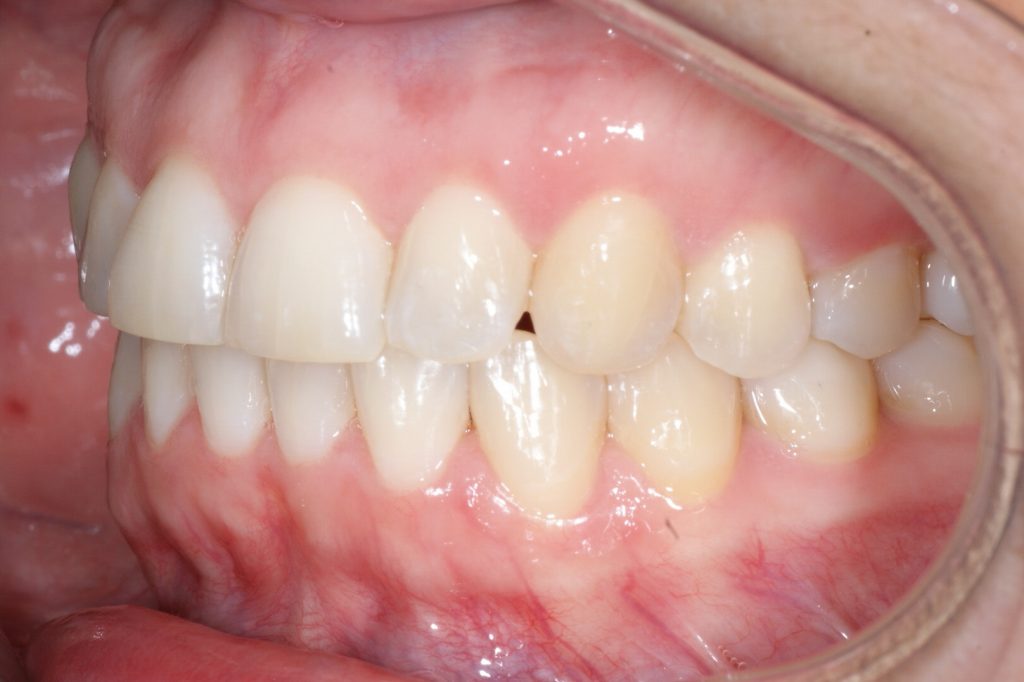

Correction d’une malocclusion de type Classe I, surplombs inadéquats et chevauchement modéré aux 2 arcades.  57 coquilles furent nécessaires pour améliorer ce sourire.  Traitement chez une adulte, réalisé en 15 mois.